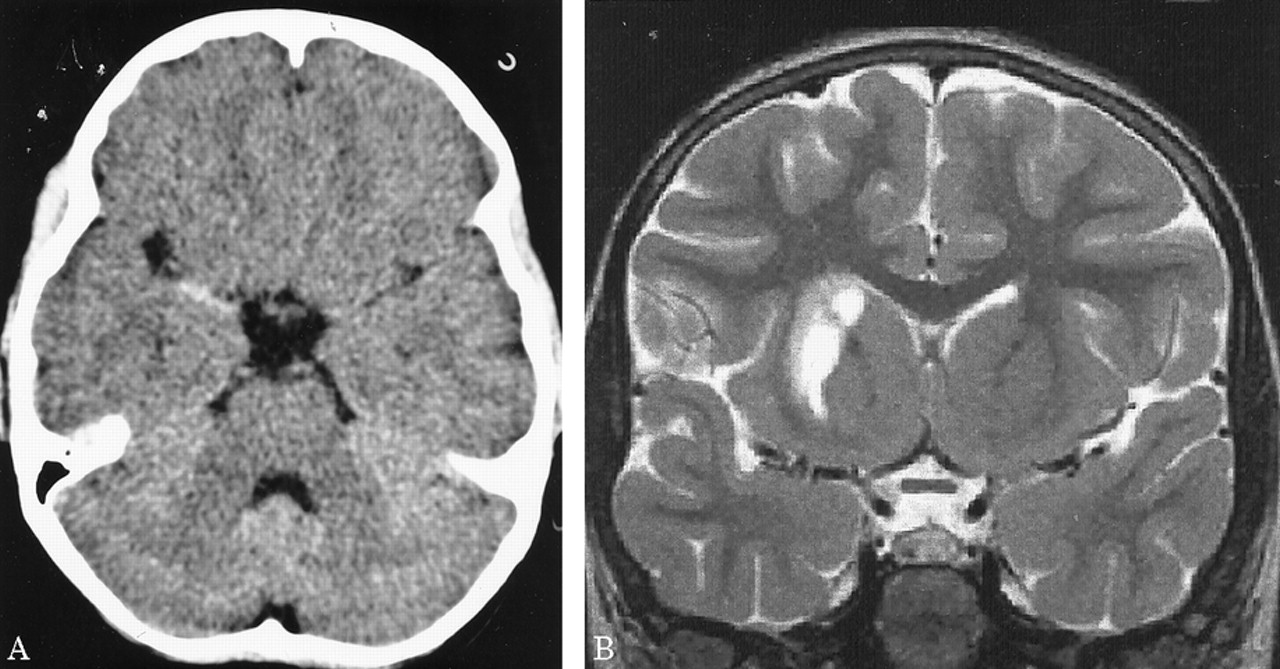

图1所示。(A)术前CT扫描显示积极的高密度的大脑中动脉(MCA)标志正确的MCA干线。(B)术后t2加权MRI 2周后动脉内的溶菌作用显示正常流动孔隙MCA干线,也是纹状体梗塞影响壳核和尾状核,保留内部胶囊。

病人气管切开后的第二天点燃,能够将第二天左胳膊和腿。一周后,这个孩子被动态。点燃了两周后,病人没有残疾在日常生活活动或休闲活动。她经历了一个最小的干扰,同时保持一个较高的位置左胳膊。考试成绩的运动强度(手测功器)和finger-hand协调(手指敲击,将挂钩孔)是在正常范围内。神经心理学评估显示没有语言障碍的迹象,认知或行为。MRI显示一个小纹状体梗死保留内囊(图1 b)。时间进程和振幅的电位诱发外展digiti最小的经颅磁刺激肌肉的皮质是在正常范围内,表示对称完整锥体束功能(延时的左臂,13.8毫秒;延迟的右臂,11.2毫秒)。灌注加权核磁共振没能证明正确的MCA血流动力学妥协领土(图3)。